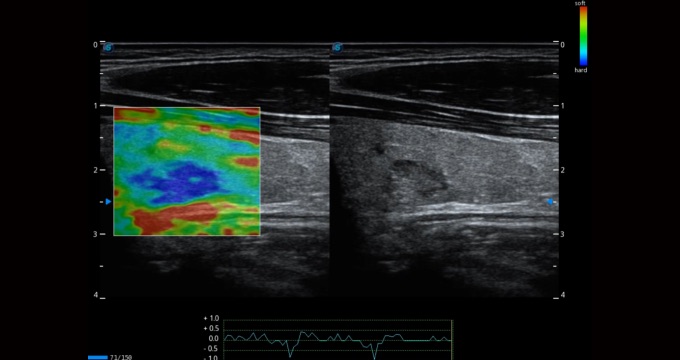

小器官应用

弹性成像支持多把探头,满足全面的临床应用。无需高频度外力作用可真实反映组织的形变,具有良好的重复性,帮助医生早期洞察潜在的病理学特征。